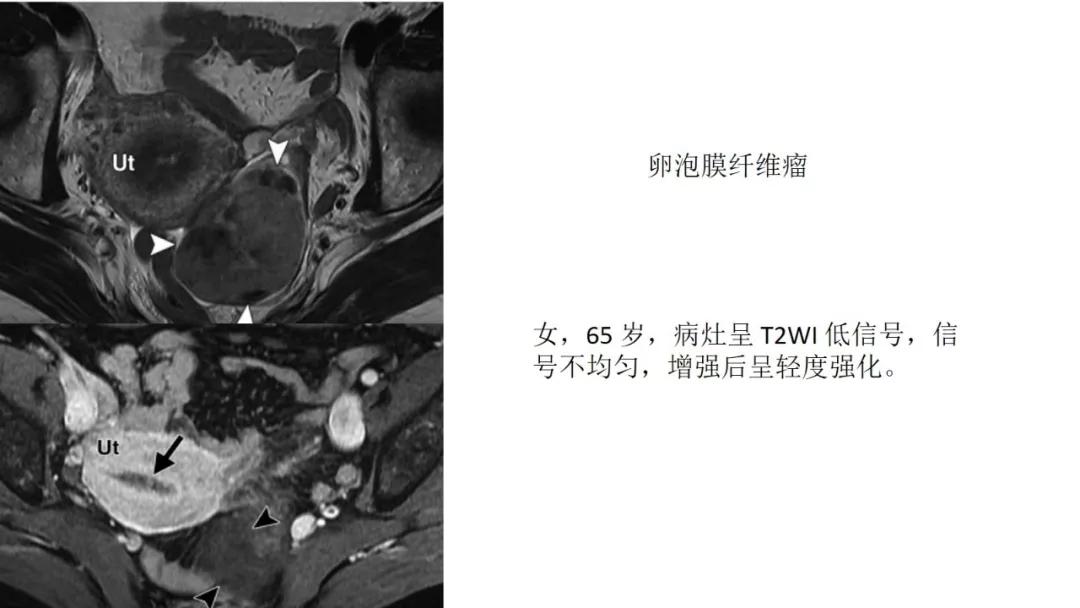

- T2WI抑脂低信号:卵泡膜细胞瘤、纤维瘤

T2WI 低信号病灶:出血、平滑肌、纤维组织、卵巢甲状腺肿(凝胶)

病理:左侧卵巢卵泡膜-纤维瘤